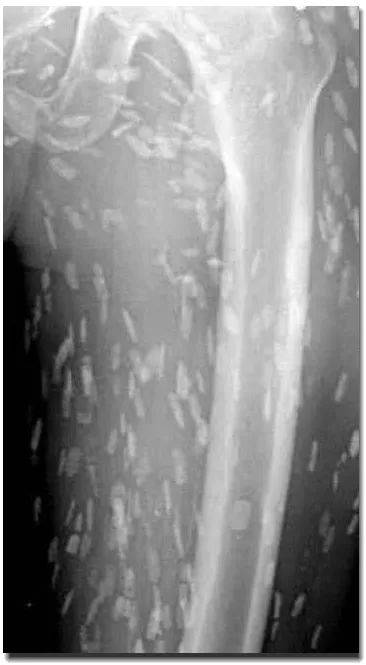

这是李教授查阅的文献当中一个成年人的大腿,肌肉中密密麻麻都是钙化

x线片提示肌肉组织中众多钙化点,检查身体其他部位发全是的,有谁见过